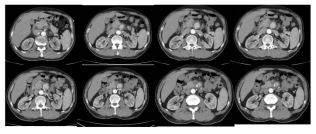

老徐,58岁,常年务农,有慢性胃炎史。两个月前,他突然开始肚子疼,还伴有黑便。“以为是胃病又犯了,忍忍就过去了。”老徐说。就这样疼了十天,忍了十天,居然自己好了。可过了一个多月,腹痛突然卷土重来,比以往任何时候都剧烈!疼得他直不起腰,连背都跟着疼,吃不下饭,睡不着觉。老徐害怕了,辗转多家医院,CT、胃镜、抽血化验都做了,可就是查不出原因。直到他来到中日医院,通过增强CT及血管外科医生的确诊,终于揭开了真相——肠系膜上动脉夹层,一个直径2.8厘米的夹层动脉瘤已经形成!

腹部ct